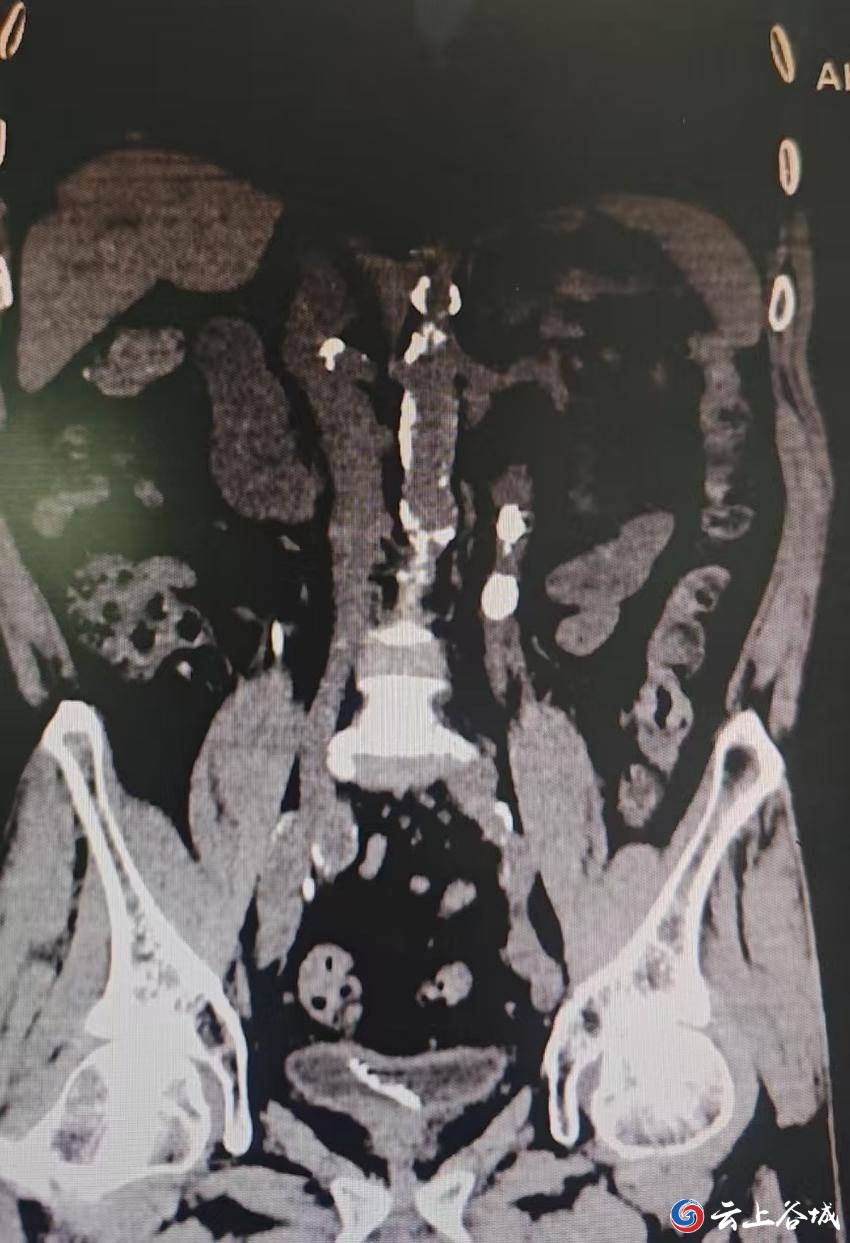

术前CT:提示多发结石 面对如此高危、复杂的病例,泌尿外科主任卢强带领团队与麻醉科共同评估手术方案,最终决定在精准胸椎旁麻醉下为患者施行手术。术中,患者全程保持清醒,生命体征平稳,手术顺利清除全部输尿管结石。手术成功得益于麻醉方式的精准选择与泌尿外科微创技术的完美配合,患者术后无需长时间禁食,早期即可进食并下床活动,实现了快速康复。